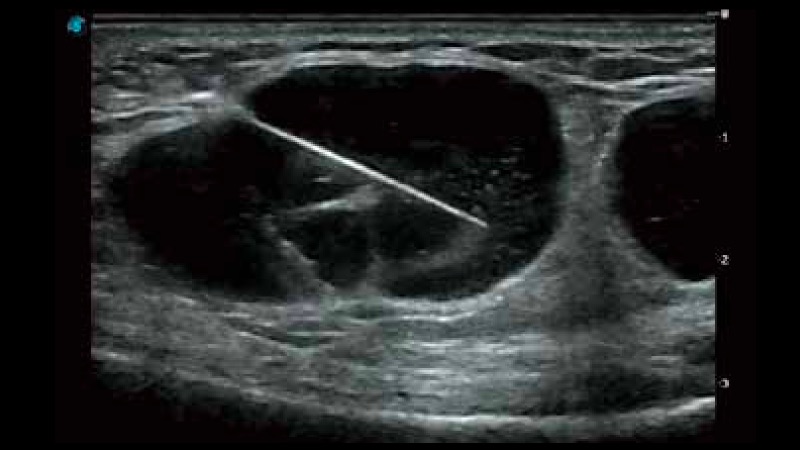

開立醫(yī)療通過不斷的技術(shù)創(chuàng)新,為大眾的生命健康提供持續(xù)關(guān)愛。P12 Plus采用全新一代超聲成像平臺,新平臺旨在將真實還原組織解剖結(jié)構(gòu)作為首要目標(biāo)。平臺采用全新集成化硬件模塊,搭載新一代芯片,系統(tǒng)性能得到大幅提升,為您的診斷提供了豐富的臨床信息。優(yōu)異的圖像表現(xiàn),豐富的探頭配置,全面的應(yīng)用功能,為您日常診斷提供了可靠的助手。